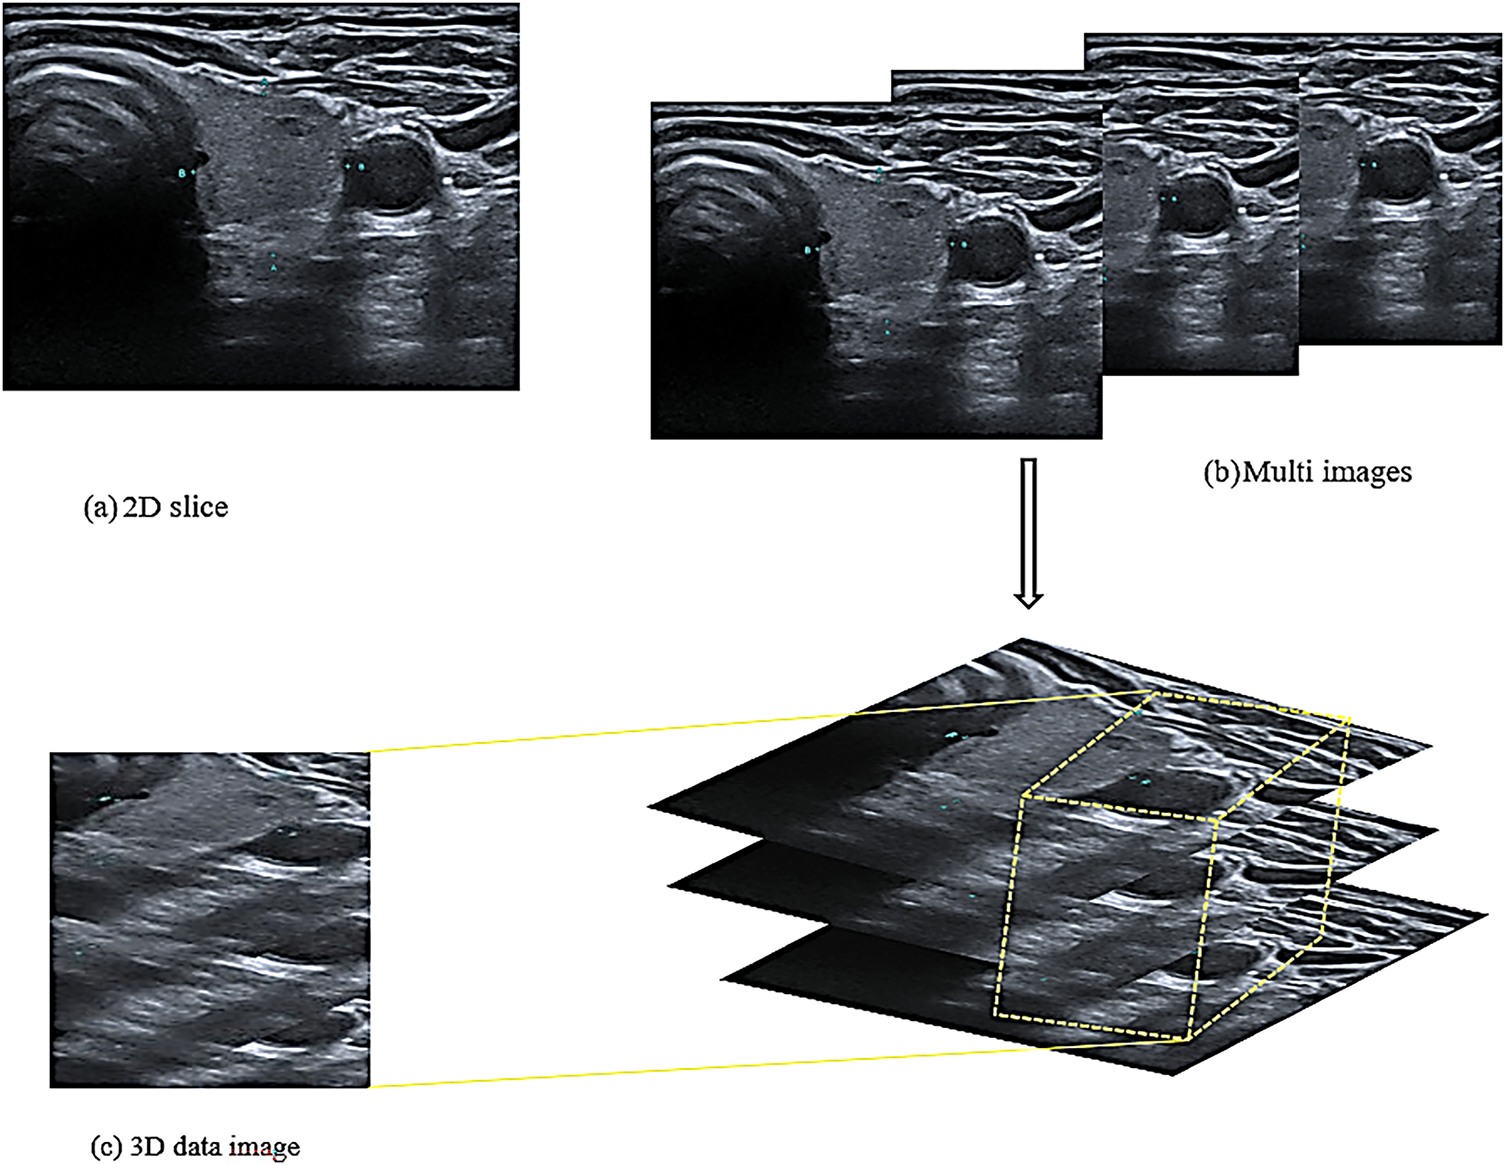

The 2D CNN is a traditional network comprising convolutional and pooling layers. The network is connected with the local region around the 2D input images [28]. The network’s sparse connection enables it to represent its inputs hierarchically. The hierarchy of the 3D CNN is an extension of that of the 2D CNN. However, the 3D CNN utilises the z cubes of the images to extract spatial and volumetric features instead of the 2D slice images [26] as shown in Fig. 2.

Figure 2: Structure of the input images

Fig. 2a shows a 2D slice that was used in the 2D CNN model for extracting the spatial features utilised in previous studies. Unlike this model, the proposed model required 3D images to extract volumetric features. Consequently, the image dataset was divided into a group of folders, each folder contained three successive images of the same patient and the exact location of the thyroid in the same direction of the image, as shown in Fig. 2b. These three images of the same nodule and location are used to extract volumetric features as a three-dimensional image. The i18LX5 probe, along with a set of standard thyroid scanning protocols, was used to scan the thyroid gland along the axial and longitudinal axes. Fig. 2b shows that the three images were treated as one 3D image and that the model extracted the spatial and volumetric features from the images based on a method reported in a previous study [30]. Accordingly, the features extracted from the images are cubes with height, width, and depth; the depth refers to the number of slices in the same folder, as shown in Fig. 2c.